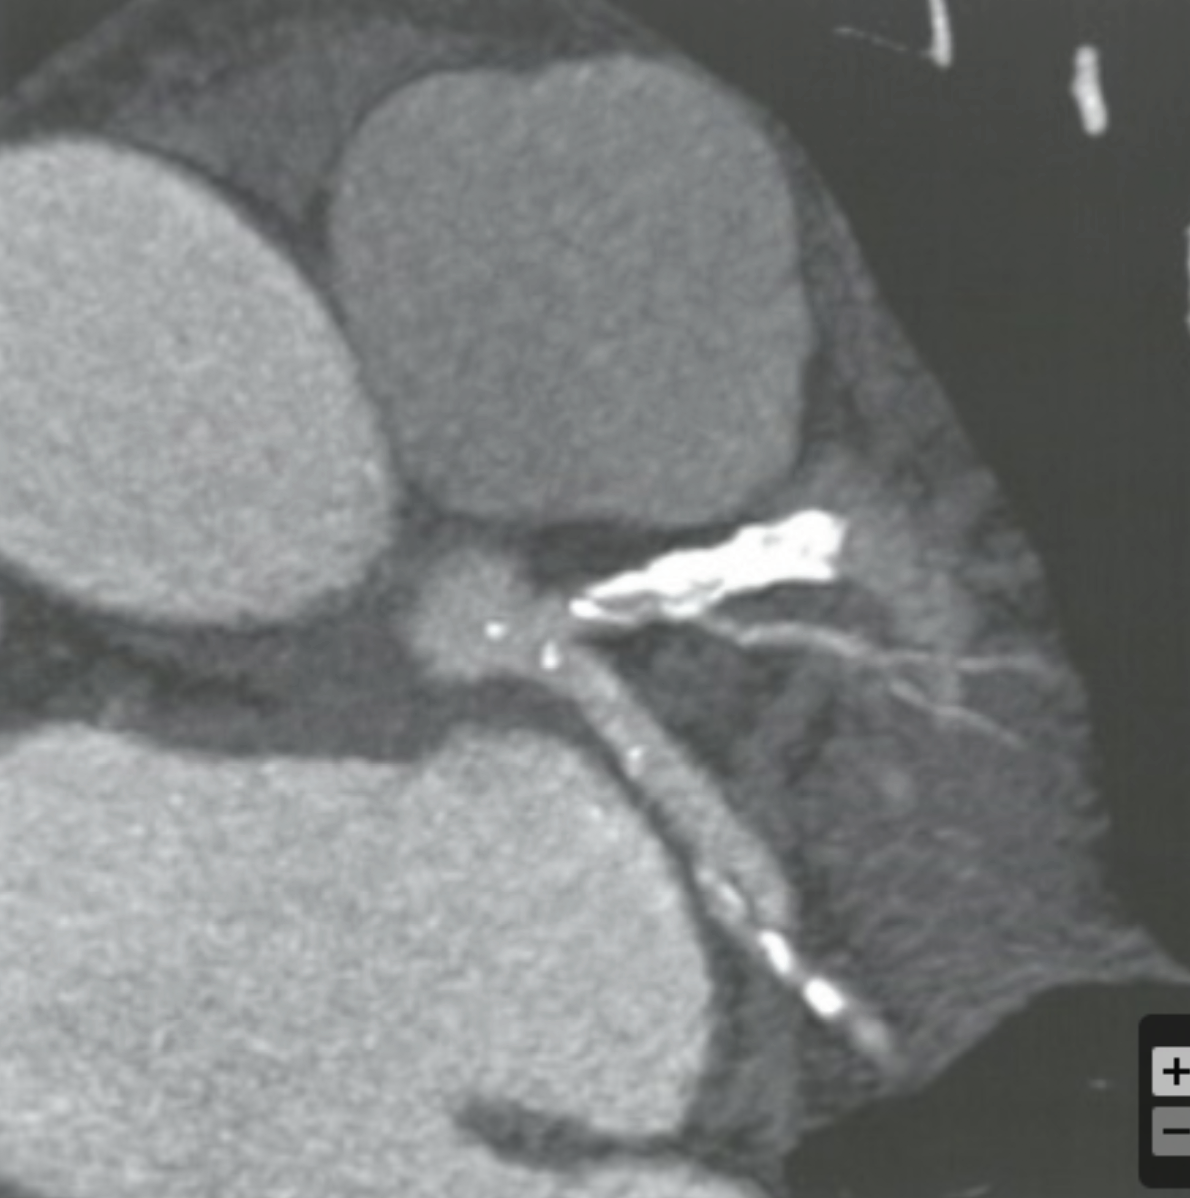

CCTA requires using thin detector collimation to avoid partial volume averaging, but the use of thin collimation comes at what cost?

Increased image noise